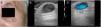

CASE 1: We present the case of an 80-year-old woman with a bluish papule of indeterminate time of evolution located on the left cheek (Fig. 1). The lesion was asymptomatic. Ultrasound showed a subdermal hypoechoic cystic lesion with turbulent color Doppler flow (Fig. 2). Venous ectasia was suspected and surgical removal was performed. The final histopathology diagnosis was hidrocystoma. CASE2: The second case was a 72-year-old man with a translucent nodule in the right temple (Figure 3). Clinical diagnosis was suggestive of a hidrocystoma. In the US exploration we also observed a hypoechoic cystic lesion with turbulent color Doppler flow (Figure 4). Final histopathology diagnosis was consistent with clinical diagnosis of hidrocystoma.